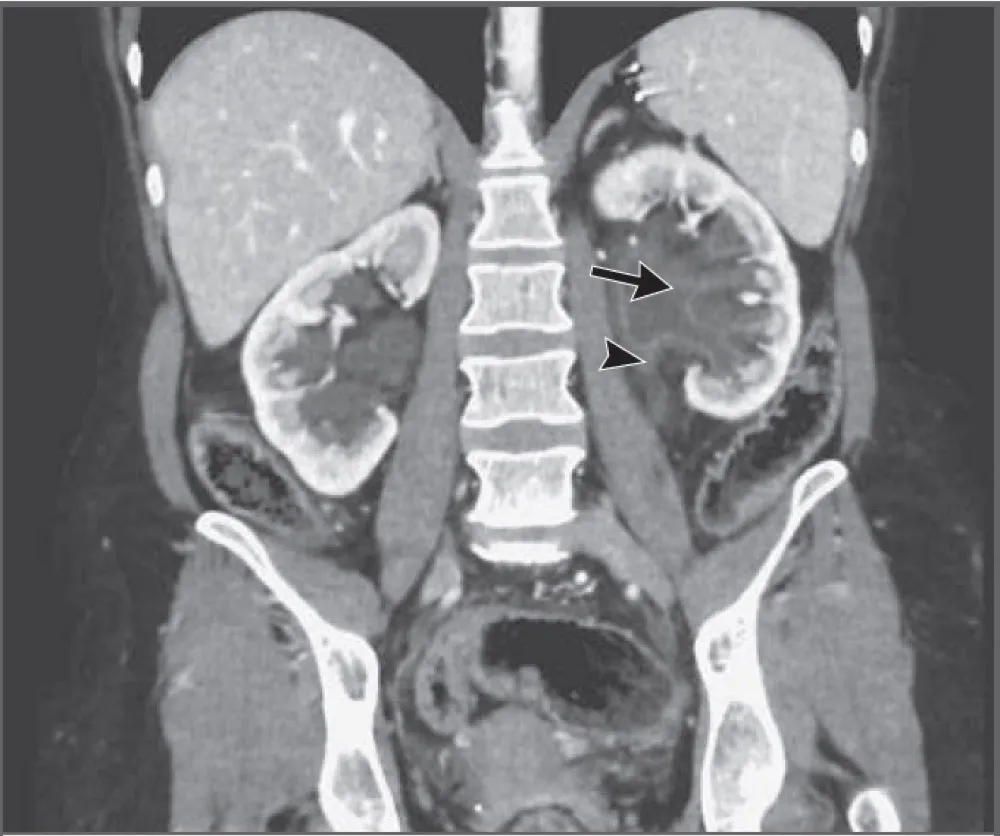

Terapia com células CAR T: uma possível revolução no manejo da Nefrite Lúpica